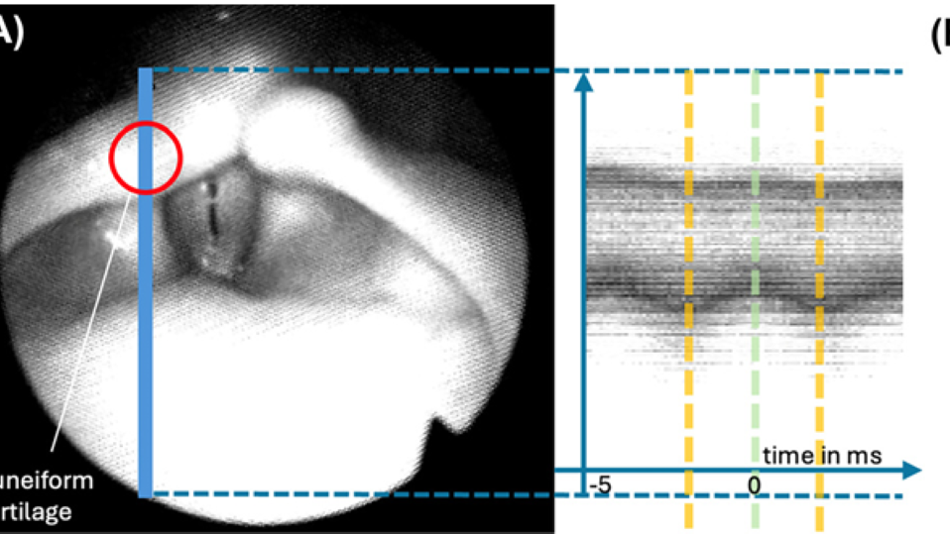

Durchschnittliche Verweildauer: 30 Minuten

Das Motto im Zentrum für Stimmforschung am Antonio-Salieri-Institut ist "Erleben-Messen-Verstehen". Im Zentrum des Beitrags steht der Vorgang, wie Studierende auf ihren eigenen Erfahrungen basierend Forschungsfragen entwickeln und sich diesen annähern. Weiterhin wird beleuchtet, welche Methoden für die Datenerfassung zur Verfügung stehen. Außerdem werden aktuelle und geplante Forschungsprojekte des Instituts vorgestellt und somit die große Vielfalt und Interdisziplinarität der Stimmforschung gezeigt.

AusstellungWomit beschäftigt sich die aktuelle Stimmforschung an der mdw? PosterausstellungThema: Kultur NaturwissenschaftenAuf Postern werden aktuelle Forschungsprojekte von Studierenden am Zentrum für Stimmforschung vorgestellt.mdw - Universität für Musik und darstellende Kunst Wien17:00 - 23:00 -